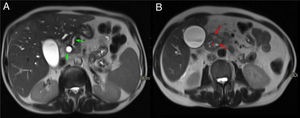

Mismo caso que la figura anterior. Cortes axiales del abdomen en secuencias T2. A) Dilatación de la vía biliar intra- y extrahepática y del conducto pancreático principal en cuerpo y cola del páncreas, con afilamiento del conducto pancreático principal en la cabeza pancreática (flechas verdes). B) Lesiones hiperintensas en la pared medial del duodeno que corresponden con lesiones quísticas (flechas rojas) con borramiento del surco pancreaticoduodenal (asterisco rojo).

Varón de 48 años con historia de alcoholismo y pancreatitis aguda de repetición. Cortes axiales del abdomen en secuencias T2. A) Dilatación del conducto pancreático principal (flecha verde). B) Borramiento de los planos grasos del surco pancreaticoduodenal y pequeñas imágenes de aspecto quístico en pared duodenal (flechas rojas). Estos hallazgos, dado el antecedente del paciente, son compatibles con pancreatitis del surco.

En ambos subtipos de PS, el aspecto medial del duodeno se encuentra engrosado con múltiples quistes en el interior de su pared y en el surco, que se identifican como focos hiperintensos en secuencias T2 (figs. 5 y 6)7. Algunos autores defienden que estos quistes intramurales del duodeno son islotes pancreáticos heterotópicos o incluso ramas ductales del conducto de Santorini dilatadas1.

En la RM, la afectación inflamatoria laminar en el surco PD se identifica como una hipointensidad de señal en secuencias T1, con intensidad de señal heterogénea en secuencias T2 y STIR (figs. 5 y 6). Dicha afectación inflamatoria presenta un realce parcheado y progresivo tras la administración de contraste debido a su contenido fibrótico7,9. En fases agudas, la afectación inflamatoria en el surco PD suele presentar una mayor intensidad de señal en la secuencia T2 por presencia de edema y líquido que, progresivamente, se transforma en tejido fibrótico en fase subaguda/crónica y en secuencias T1 y T2 presenta una menor intensidad de señal debido a la atrofia parenquimatosa y la fibrosis. Por tanto, la secuencia T2 resulta muy útil para inferir el grado de actividad7.